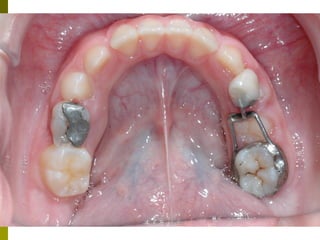

Πρώτη σχολική ηλικία 6-10 ετών

   Αρχίζει αλλαγή των τομέων και η ανατολή των

πρώτων μόνιμων γομφίων (μεικτή οδοντοφυΐα)

   Παρατηρούμε η αλλαγή δοντιών να γίνεται με τη

σωστή σειρά και στη σωστή θέση

   Μπορεί να χρειαστεί πρώιμη ορθοδοντική

θεραπεία, για να αποφευχθούν πιο δύσκολες και

πολύπλοκες εργασίες αργότερα

   Διατήρηση νεογιλών δοντιών στον οδοντικό

φραγμό μέχρι τη φυσιολογική τους απόπτωση